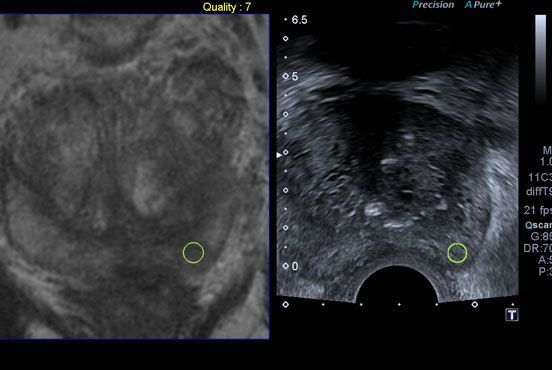

A more elegant approach is to get the computer in the ultrasound machine to match the MRI pictures to the ultrasound picture. Once this has been done the US and MRI pictures move together in real time, side by side. The abnormal area on the MRI is marked and the corresponding area on the ultrasound displayed. To do this the machine records the movement of the ultrasound using a micro GPS tracking system. For this to work you cannot move once the initial fusion has been set up. To make this easier a little bit of sedation may be used.

An MRI picture is on the left, the ultrasound picture on the right. The yellow circle shows the target area.